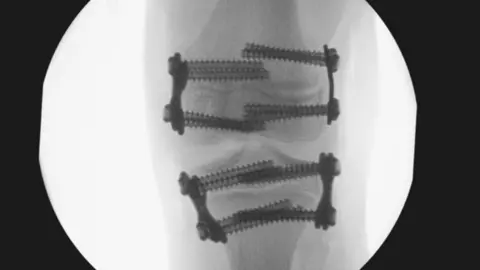

But the assessment said metal plates inserted into her longer leg to stop it growing were too big, causing pain and requiring replacement.

Reviewers said the plates used to prevent bone growth in Amy's left knee were too big and not positioned correctly